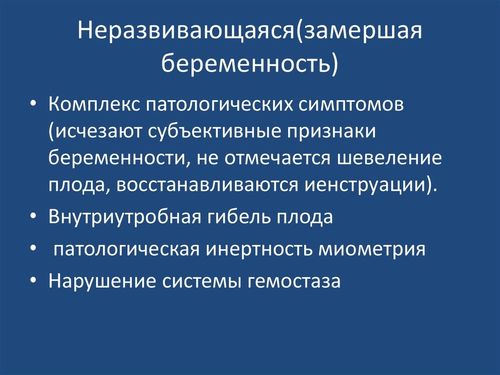

Замершая беременность представляет собой одно из двух возможных состояний. В первом варианте яйцеклетка успешно оплодотворяется и прикрепляется, однако по различным причинам эмбрион не продолжает свое развитие. В этом случае формируются внезародышевые структуры, такие как хорион, оболочки и плодный мешок. Во втором варианте яйцеклетка также прикрепляется, и на определенном этапе эмбрион развивается нормально, но затем его развитие останавливается, и он погибает. Первый случай иногда называют пустым плодным яйцом.

Это состояние довольно распространено и чаще всего наблюдается на ранних сроках, в первую половину первого триместра. Тем не менее, оно может возникнуть и позже, хотя и реже, вплоть до нескольких недель до родов. При этом у плода прекращает прослушиваться сердцебиение, что свидетельствует о его гибели.

Остановка развития плода сопровождается рядом характерных признаков, однако на ранних сроках выявить это практически невозможно. Симптомы могут отсутствовать полностью. На более поздних сроках женщина, как правило, сразу замечает отклонения от нормы.

Симптомы и признаки

Замирание первого триместра характеризуется слабо выраженной симптоматикой. Сначала, после остановки развития, у пациентки сохраняются все признаки нормально протекающей беременности – токсикоз, нагрубание молочных желез, даже тест способен оказаться положительным, а матка увеличена. Но как только происходит отслойка плаценты, симптоматика начинает быстро исчезать.

Появляются характерные признаки замирания:

- Боли внизу живота, часто – схваткообразного типа. Вызываются сокращениями матки, когда организм пытается избавиться от плода.

- Тянущие боли также могут возникать.

- Резкое исчезновение токсикоза.

- Уменьшение молочных желез, снижение их чувствительности.

- Специфические кровянистые выделения из влагалища.

- Иногда в выделениях явно видна примесь гноя, что говорит о давно уже замершем вынашивании, а организм избавляется от фрагментов разложившегося плода.

- Для второго триместра явным симптомом является прекращение активности, движений, перемещений плода. Одновременно с этим окружность живота может продолжать увеличиваться, так как растут внутриплодные оболочки.

- Базальная температура при замершей беременности понижается.

Иногда признаком патологии способна быть лихорадка – сильное повышение температуры тела происходит, когда плод начинает разлагаться.